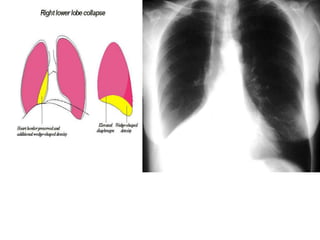

Radiologic signs of collapse

The term collapse is used when a whole lobe or lung is involved.

Atelectesis is defined as diminished volume

affecting all or part of a lung, whichmay or may

not include loss of normal lucency in the affected

part of lung .

Pulmonary atelectasis can be divided into six

types, based on mechanism: resorptive, adhesive,

compressive, passive, cicatrization, and gravity-

dependent

LOBAR ATELECTASIS

Radiologic signs of lobar atelectasis :- Direct

or Indirect .

Direct signs include increased opacification

of the airless lobe and displacement of

fissures.

Indirect signs include displacement of hilar and

cardiomediastinal structures toward the side of

collapse, narrowing of the ipsilateral intercostal

spaces, elevation of the ipsilateral

hemidiaphragm, compensatory hyperinflation

and hyperlucency of the remaining aerated

lung, and obscuration or desilhouetting of the

structures adjacent to the collapsed lung

(eg, diaphragm and heart borders). Additional

radiologic features vary according to the site of

atelectasis.